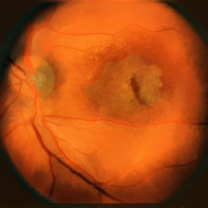

Figure 7: Three FA fundus images with symptom of GA and corresponding generated images. (a), (b), (c) Original images. (d), (e), (f) Generated images.

Furthermore, generated images from FA images are presented in Fig. 6 and Fig. 7. Results in the images are nearly identical to the original images, because original networks are applied to stylize color images. However, six generated images contain more concise features than the original ones, which helps ophthalmologists make better judgments. Therefore, this style transferring networks can fulfill edge sharpening and enhancement of contrast. No matter which kinds of images are generated, advanced features in new disease images still exist. Furthermore, analyses of image performance by EyeNet and CAMs for prediction are presented in a later section.